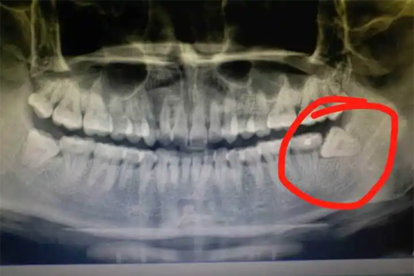

反复发作的智齿冠周炎建议拔除患齿。传统拔牙术适用于完全萌出智齿,微创拔牙术适合埋伏阻生智齿。急性期需先进行龈瓣切开引流,待炎症控制后行牙槽骨修整术。